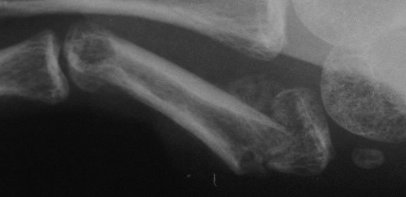

| A second case, five weeks after injury with early callus, treated with similar technique after percutaneous fracture mobilization with a small elevator. |